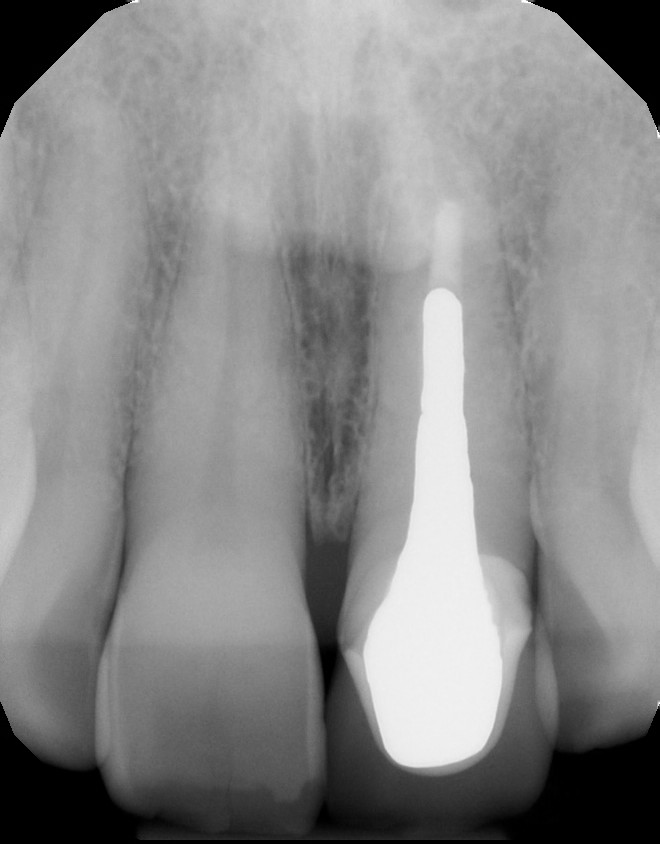

The comprehensive oral examination, which included radiographs, revealed nothing that would contraindicate this treatment plan (Fig. 2). In fact, the previous endodontic treatment was acceptable, and the post was well-adapted to the tooth. The risks and benefits of removing the post were discussed with an endodontist and ultimately the patient, and it was decided to leave the existing cast post and core in place. However, doing so would create prosthetic challenges, including identifying a material that offered an esthetic outcome while blocking out the dark-colored post and core. For this reason, a full-coverage crown fabricated from zirconia was recommended and accepted by the patient.